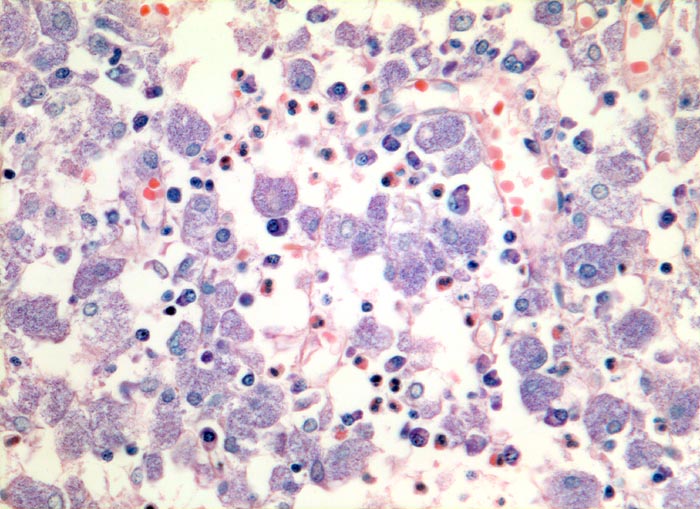

PathoPic – image database / PathoPic ID 3728 - atypische Mykobakteriose (Mycobacterium avium intracellulare)

atypische Mykobakteriose (Mycobacterium avium intracellulare)

Entzündung infektiös

Lymphknoten, Kopf-cervikal

Grossleibige histiozytäre Zellen mit fein granuliertem Zytoplasma. Daneben wenig Plasmazellen und Granulozyten.

Ziehl-Neelsen Färbung: die Histiozyten sind voll von säurefesten Stäbchen.

Seit 3 Jahren HIV positiv.

Das Bild der mykobakteriellen Histiozytose wird vor allem durch atypische Mykobakterien verursacht, vereinzelt aber auch durch Mykobakterium tuberculosis.

Histologie

320